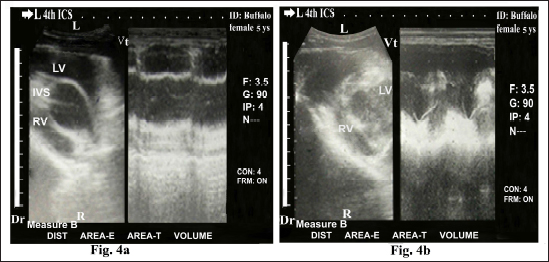

Ultrasonography of the normal heart in the healthy buffaloes was imaged from the left fourth ICS in midway between the elbow point and shoulder point as the transducer directed dorsally and slightly cranially toward the left fifth ICS showed the four chamber view either in diastole (Fig. 2a and b) or systole status (Fig 2c and d); right atrium (RA), right ventricle (RV), tricuspid valve (TCV), left atrium (LA), left ventricle (LV), mitral valve (MV), and interventricular septum (IVS).

Fig. 2. Echocardiogram of caudal long axis view in adult healthy female non-pregnant (4-year-old) buffalo (left side) during diastole (a and b) and systole (c and d) using a 3.5 MHz sector 2-D-gray scale transducer (B-mode and M-mode). It was imaged from the left fourth ICS in midway between the elbow point and shoulder point as the transducer directed dorsally and slightly cranial toward the left fifth ICS. It showed a normal heart with regular, strong contractions and clear margins. The four chambers view was imaged where it included the RA, RV, TCV, IVS, LA, LV, LV, MV. Echocardiographic dimensions, either in diastole or in systole, were also visualized, including right ventricular diameter (RVD), right ventricular wall thickness (RVW), right atrial diameter (RAD), right atrial wall thickness (RAW), IVS, left ventricular diameter (LVD), left ventricular wall thickness (LVW), left atrial diameter (LAD) and left atrial wall thickness (LAW). Dr; Dorsal. Vt; Ventral. R; Right. L; Left.